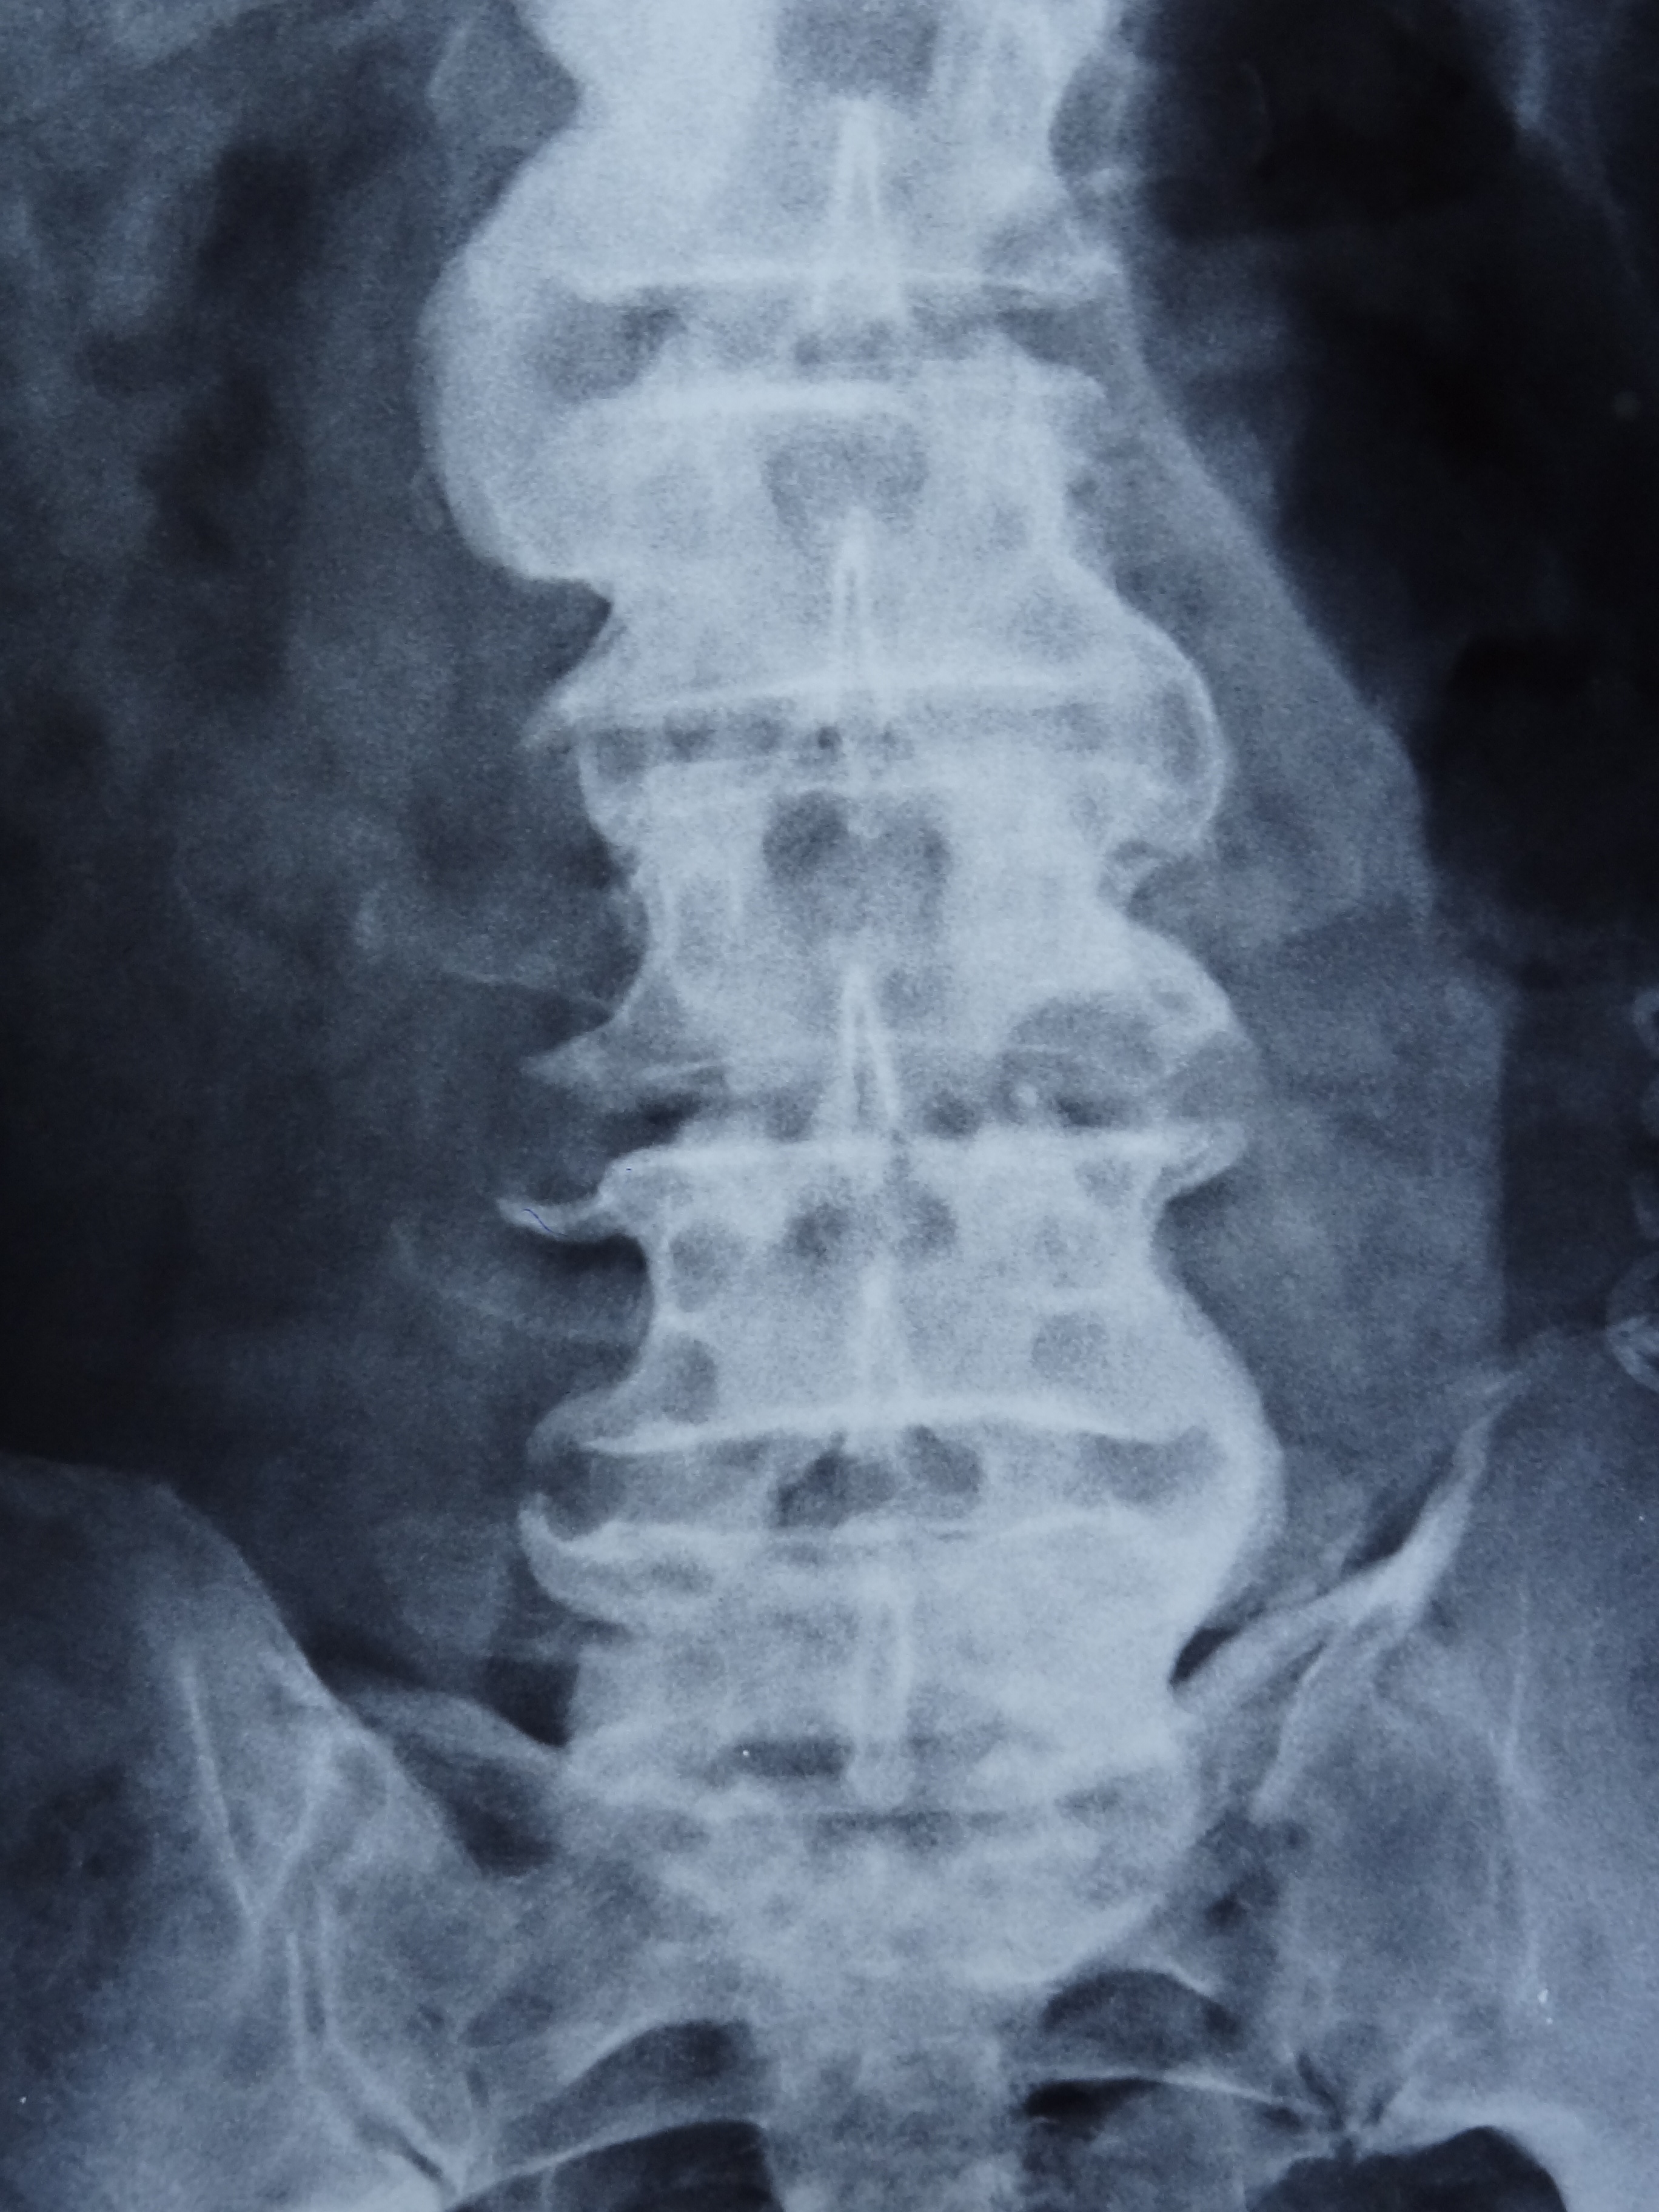

A 70-year-old diabetic and hypertensive male patient visited our clinic with complaints of non-inflammatory back pain since two years. He was heavy built with a BMI of 29 kg/m2. Physical examination revealed limitation of flexion, extension, and lateral flexion of lumbar spine. X-ray of spine revealed flowing calcification of anterior longitudinal ligaments from cervical to lumbar spine with claw osteophytes giving rise to characteristic ‘Melting Wax’ appearance (Panel A: fig A- cervical anteroposterior (AP), fig B- cervical lateral , fig C- lumbar AP , fig D- lumbar lateral) (Panel B: fig E- thoracolumbar AP, fig F- thoracolumbar lateral). Sacroiliac joints were normal (Panel A: fig C- white arrow). The diagnosis was diffuse idiopathic skeletal hyperostosis (DISH or Forestier’s disease) and symptomatic treatment was initiated.